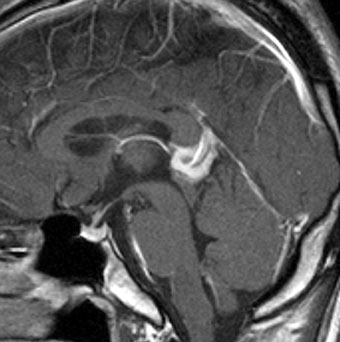

軽度の複視のみで発症した20代前半男性です。右上のように松果体腫瘍の前に割れ目が入るように第3脳室があり,両側視床に浸潤するために軽度の視床浮腫があり,ガドリニウムで強く増強され一部にのう胞があります。これだけでもgeriminomaにかなり特有の所見です。さらに,灰白隆起(矢印)のところに小さな神経下垂体germinoma腫瘍があります (bifocal tumor)。HCGは測定限界以下,AFP 2.5で,水頭症はありません。全ての臨床所見がgerminomaであることを示しています。

生検病理診断をしないでICE化学療法を1コース終えた後の画像です。腫瘍は消失しています。これでgerminomaであることが確認できたので,ICE化学療法を2コース追加して,25.2グレイの全脳室照射をして治療を終了しました。